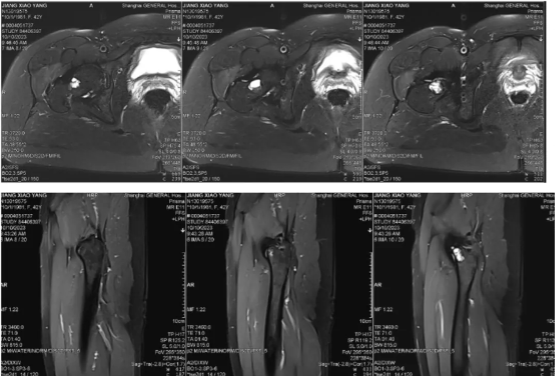

图2:术前MRI提示肿瘤为囊液性病灶为主,良性可能大